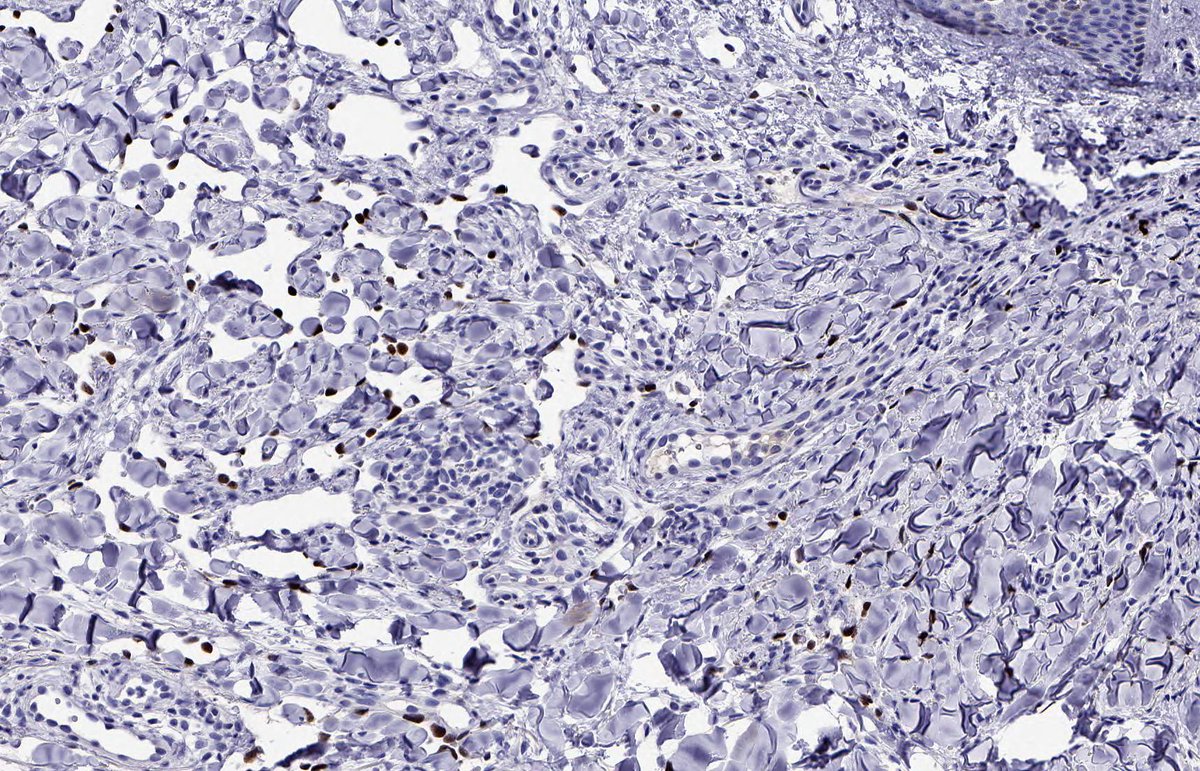

KAPOSI SARCOMA: IHC: HHV8. NB: ectatic, irregularly shaped, thin-walled vessels; collagen dissection; so-called 'promontory sign'; attenuated endothelial cells with eosinophilic cytoplasm; hyperchromatic nuclei showing mild atypia and inconspicuous mitotic activity.

2

28

69